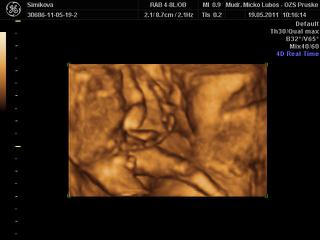

ahojte baby.tak som domaa som neopisatelne stastnaaaaa...babatko je v poriadku ma asi 16cm a vazi okolo 149g.som straassssnneeee radaaaaa. je to zazitok na cely zivot.stale tomu nemozem uverit ako krasne sme si to s malou pozerali.podla velkosti vychadza ten termin 11.11.je zdravucke a to som stastnaaaaaaaa. 😀 😀